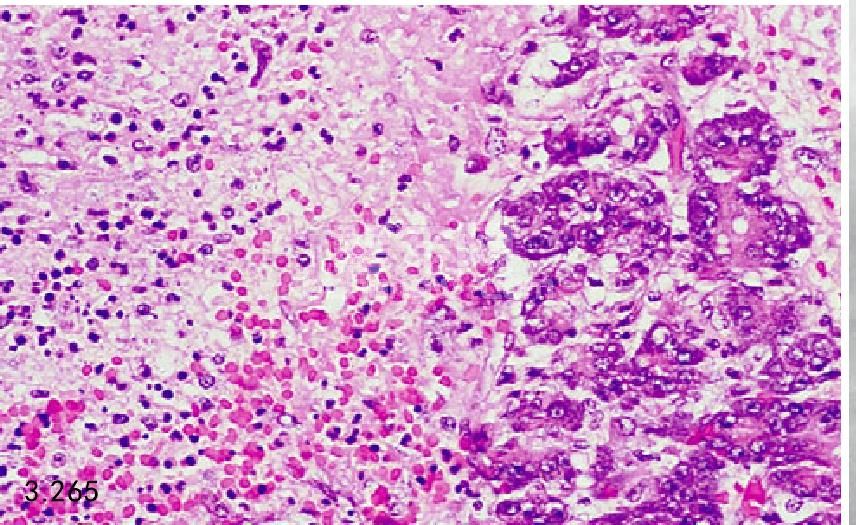

图3.265和图3.266 上图患犬胰腺的组织病理学图片显示为腺体坏死、出血、水肿,由中性粒细胞和巨嗜细胞的炎性浸润(H&E)。